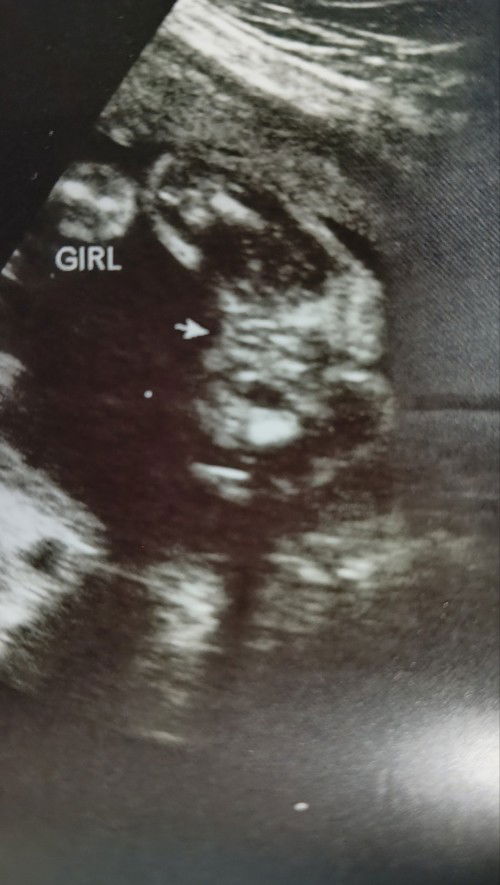

GENDER @23 WEEKS

Mga Mii sure napo kaya yung Gender ni Baby? 23 weeks po nung nakita Gender niya via Fetal Biometry Ultrasound π Nagtanong naman ako sa OB if sure na yung Gender sabi usually 23 weeks kita na naman daw talaga yung Gender ni Baby πΆ Or magpa Ultrasound nalang ako for Gender ni Baby para sure? Ps: 28 weeks napo ako today π Nanghihinayang kase ako sa 800 Pesos pang Ultrasound pandagdag nalang sana sa pagbili ng gamit ni Baby Girl βΊοΈπ#pregnancy #advicepls